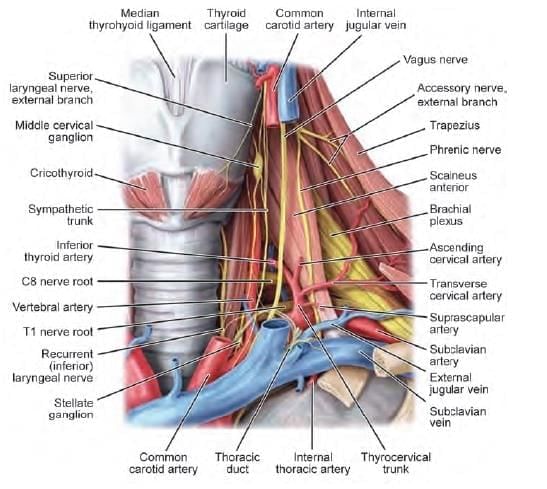

Which of the following arrow marked nerves, if injured present with paradoxical breathing? (INI-CET Nov 2020)

Inferior thyroid artery supplies: (INI-CET Nov 2021)